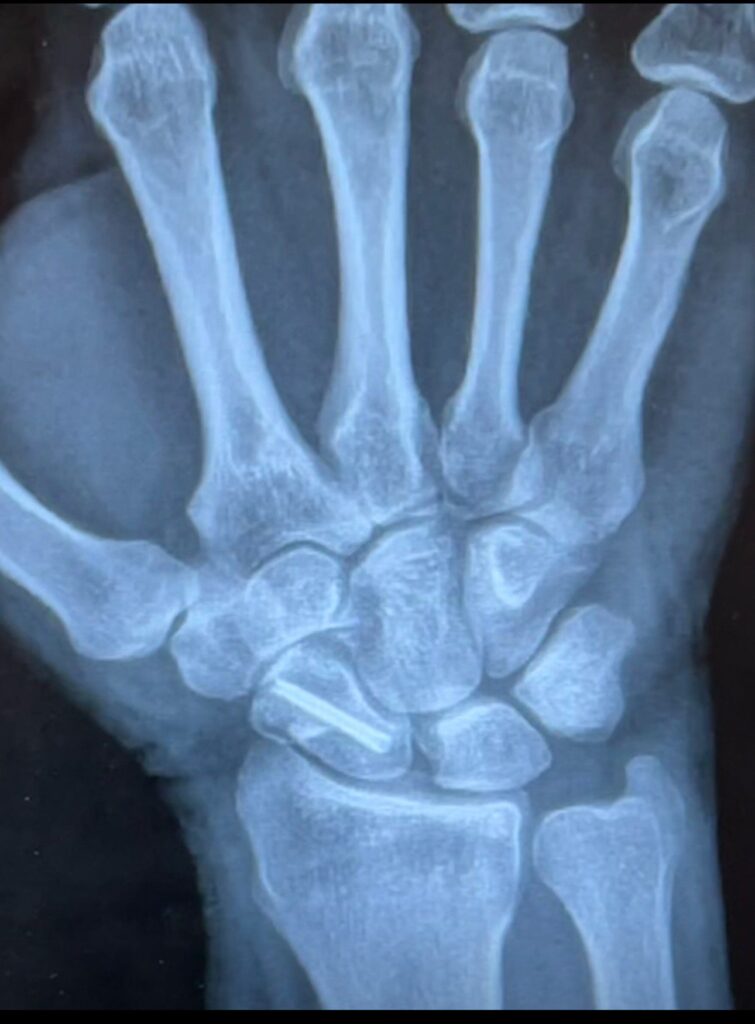

After being hit by a vehicle while riding my bicycle, I suffered a broken right wrist and a torn bicep tendon—injuries that not only affected my daily life but also threatened my ability to compete in one of my greatest passions: bowling.